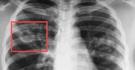

Платформа для поддержки принятия врачебных решений «Цельс» начала анализировать результаты компьютерной томографии головного мозга, сообщили в пресс-службе Платформы Национальной технологической инициативы (НТИ).

«Искусственный интеллект ищет очаги кровоизлияния и в течение нескольких минут выдает результат, помогая врачам быстрее принять решение об экстренной помощи. Кроме того, ведется доработка системы для выявления рака мозга при проведении КТ- исследований», — отметили в НТИ.